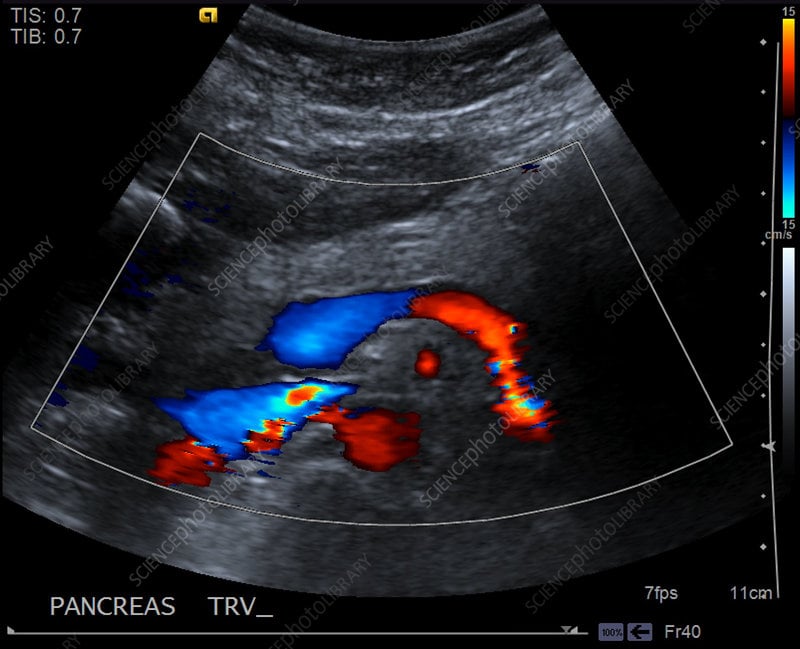

Trans Pancreas

Trans Pancreas w/ color